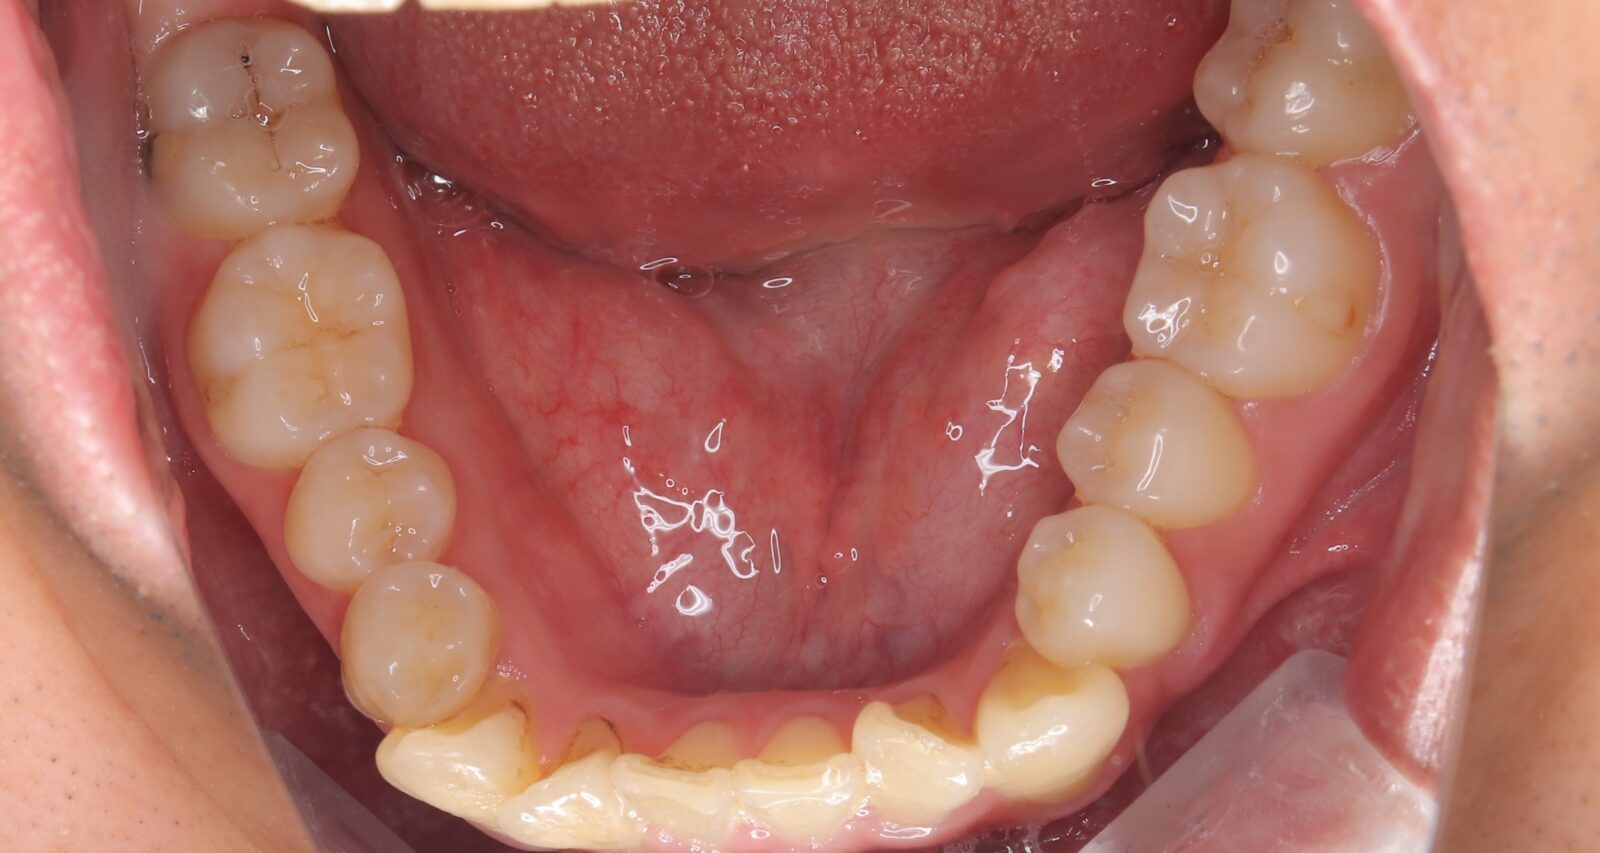

インビザライン(全体矯正)+ホワイトニングコースの症例

歯の裏に歯が隠れてしまっていたため、全体矯正(非抜歯+遠心移動)で美しく改善。

・費用:935,000円(税込)

・治療期間:30ヶ月

・通院回数:30回

・35歳女性

-リスクと副作用-

・長時間マウスピースを装着するため、むし歯や歯周病のリスクがある。治療後はリテーナーを装着しないと後戻りしてしまうリスクがある。

・ホワイトニング剤の影響で知覚過敏が起こる可能性がある。色が徐々に戻る可能性がる。